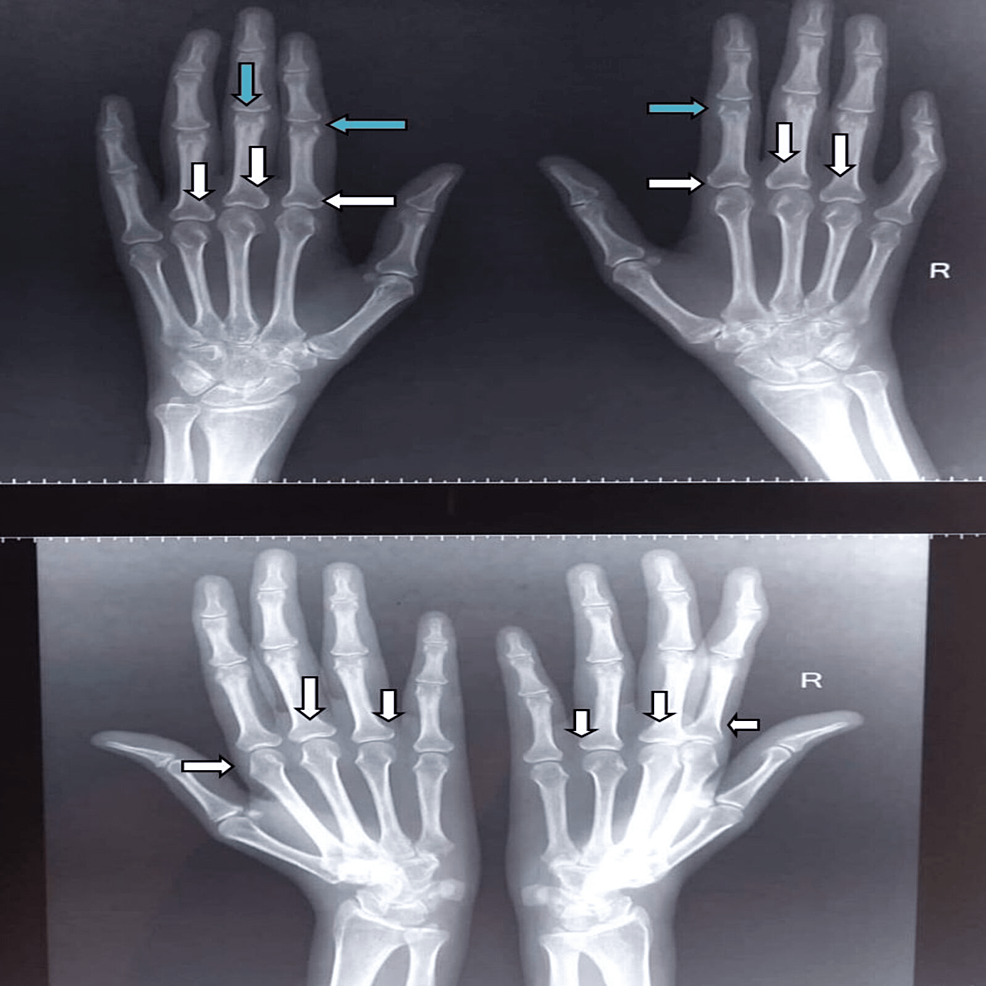

Radiographic image of a 50yearold woman's right hand. Bilateral What Is Juxta Articular Osteopenia Normal fat planes may be obliterated, which occurs as a result of joint effusion, edema, and tenosynovitis. Compounded by corticosteroid therapy and disuse. Thereafter, periarticular osteopenia may develop. Ct shows osteopenia with cortical thinning, and mri shows findings consistent with diffuse edema in the femoral head, neck and intertrochanteric areas. If it’s not treated, osteopenia can become. Articular bone erosion. What Is Juxta Articular Osteopenia.